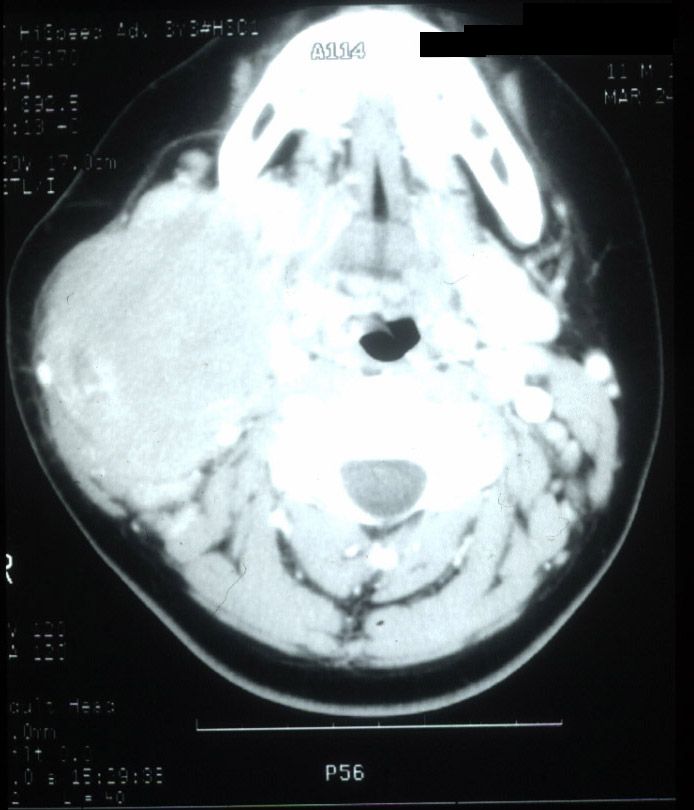

Axial CT scan illustrates a large right cervical mass. This child was diagnosed with Burkitt's lymphoma.